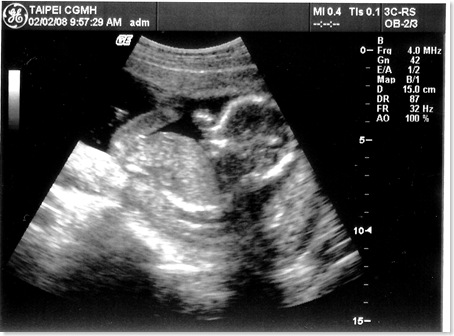

[產檢] 17週 寶寶頭大不是我的錯~~ ><

地點 02/02台北長庚 例行產檢

週數 17週

身長 15cm 體重約200g  ;  OK

心跳 150下/分鐘 OK

這星期主要還是看看超音波

量量寶寶的身長和估算體重有沒有在正常範圍

老婆邊照邊說寶寶頭很大..

沒想到醫生還跟著老婆瞎起鬨

說寶寶頭大像爸爸喔!!!   (明明寶寶頭的比例本來就比身體大得多...)   生氣...

這次照的超音波照也很清楚喔!!  真讚!!

寶寶還擺出鹹蛋超人的手交叉的動作..  五根手指己經看得清清楚楚了